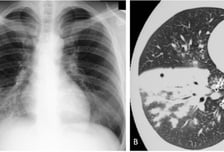

중국을 휩쓴 마이코플라스마(마이코플라즈마) 폐렴균 감염증이 국내에서도 빠르게 확산하고 있다. 최근 4주간 감염자가 2배(10월 셋째 주 102명→ 11월 둘째 주 226명)나 증가했다. 특히 국내 환자 10명 중 8명이 '12세 이하' 어린이라는 점에서 학부모들이 긴장하고 있다. 게다가 증상이 감기와 비슷해 초기 진화를 못 할 가능성이 큰 데다, 독감·코로나19와 동시다발적으로 걸리면 위중증으로 나빠질 수 있어 주의해야 한다. 과연 마이코플라스마 폐렴균 감염증(이하 마이코플라스마 폐렴)이 뭐고, 증상은 감기와 어떻게 다를까? 마이코플라스마 폐렴은 마이코플라스마 폐렴균(Mycoplasma pneumoniae)으로 발생하는 급성 호흡기 감염증으로, 우리나라에선 법정 감염병(제4급)으로 관리한다. 이 균에 감염된 사람의 침이 다른 사람의 호흡기로 튀거나 이동할 때 잘 감염된다. 몸속에 들어온 이 균은 평균 2~3주간 잠복했다가 증상으로 나타난다. 감기와 증상이 비슷한 듯 다르다. 감기는